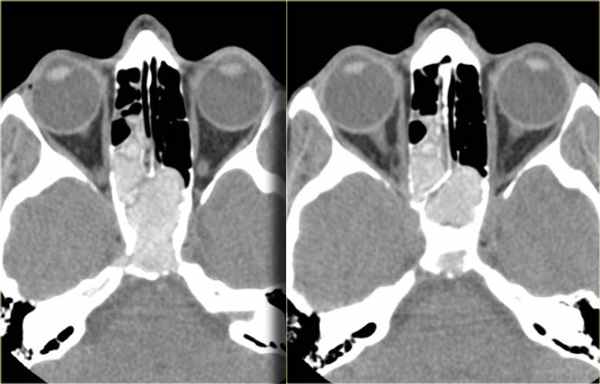

Не стоит забывать и о Ecchordosis physaliphora* (Клин. наблюдение 3). Это врожденная доброкачественная гамартома, которая формируется из нотохордальных зачатков и может встречаться в любой кости, начиная от основания черепа, оканчивая крестцом. Как правило, протекает бессимптомно и является случайной находкой при проведении КТ или МРТ. Выглядит как дефект ската, четко отграниченный и с гладкими контурами, без агрессивного компонента [5]. В литературе описан случай симптомного течения Ecchordosis physaliphora [6], однако, это, скорее, исключение из правил.